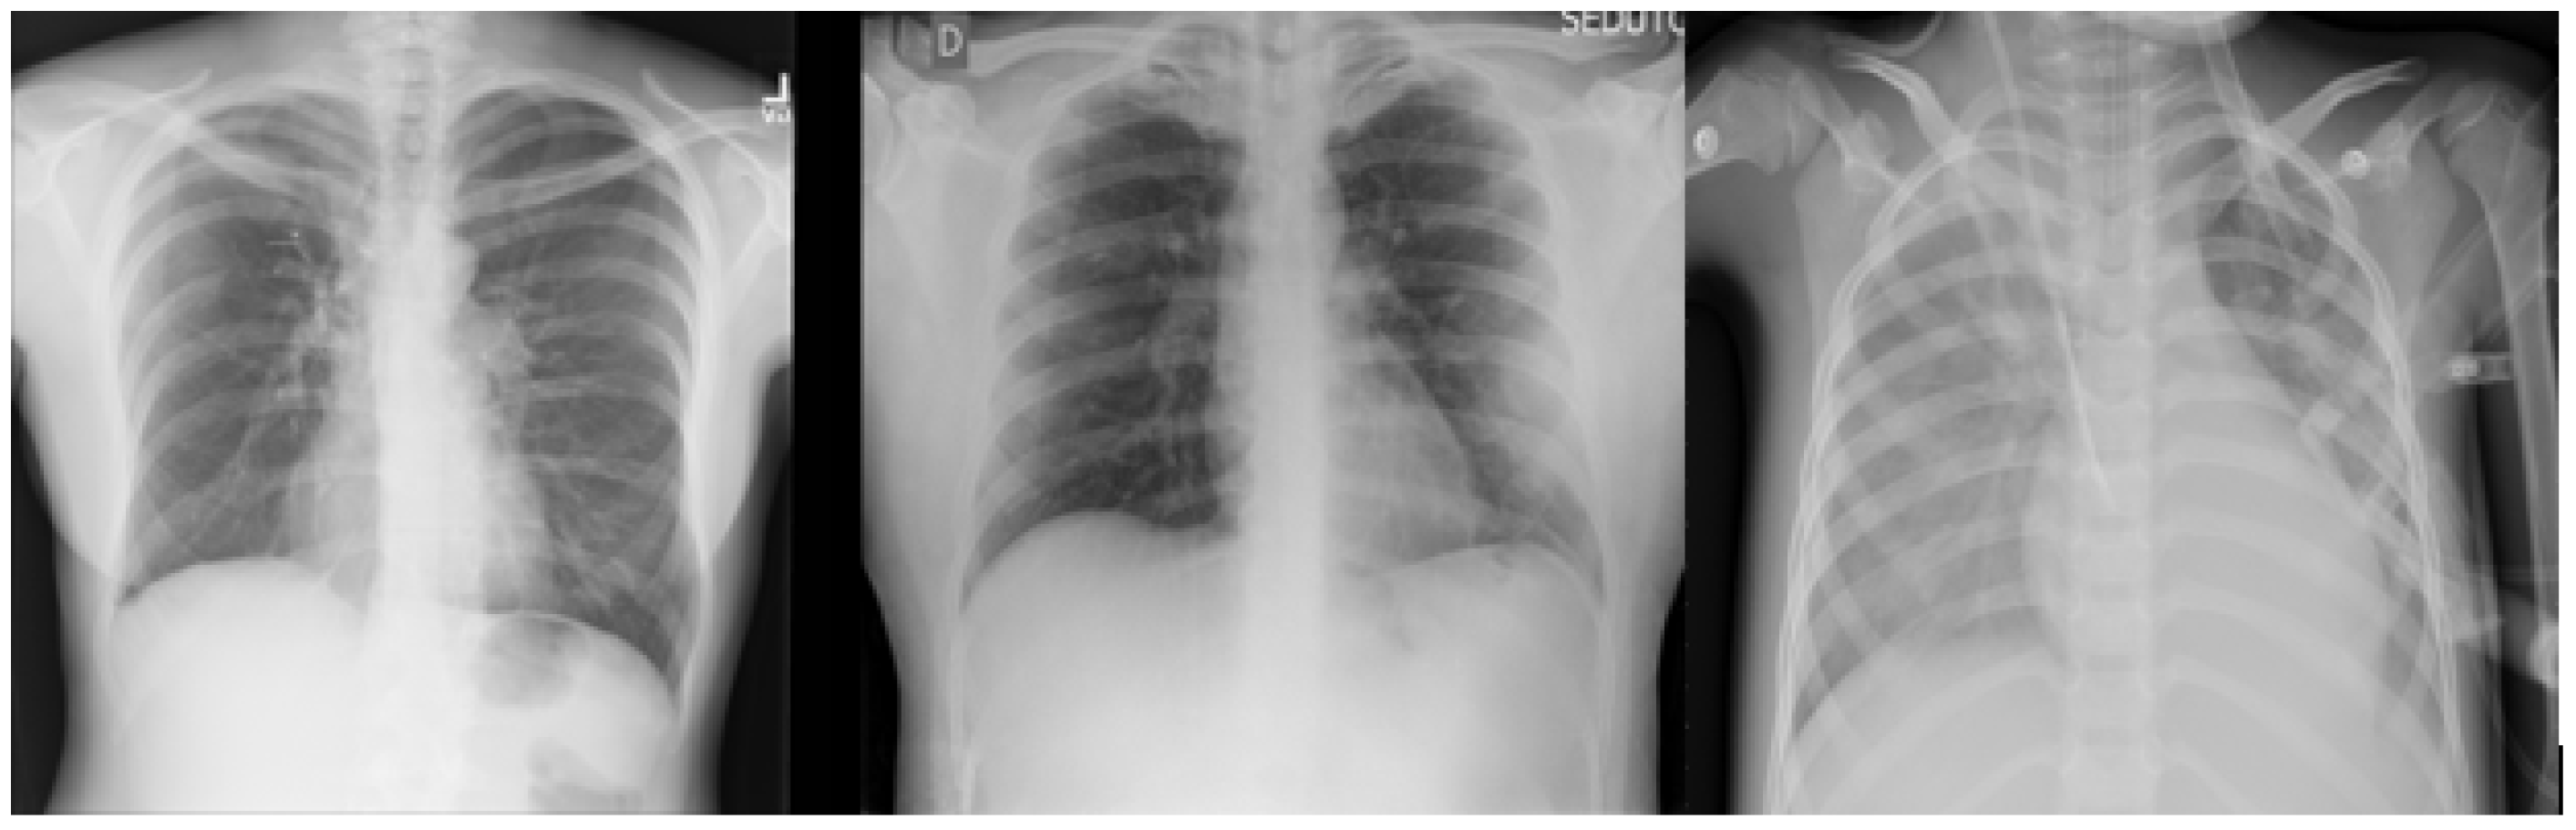

As shown in Figure 4, we applied several data-augmentation techniques, such as scaling, rotation, multiplication, addition, horizontal and vertical flipping, Gaussian blur, shearing, and so on. After applying the augmentation techniques, the number of images reached 216,000 images; we computed this number by multiplying the number of original training images by the number of augmentation techniques used, which was 15. Finally, we added the results to the number of original training images number ((13,500 × 15) + 13,500 = 216,000). Table 4 illustrates the description of the image-augmentation techniques used.

Figure 4. Image-augmentation techniques.